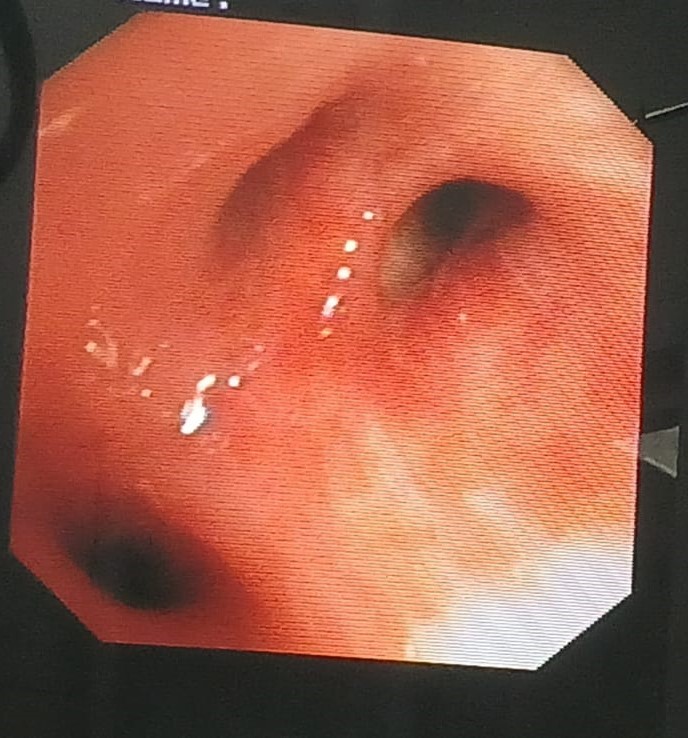

draurtecho Ene 17, 2025 Fibrobroncoscopia diagnostica La broncoscopia es un procedimiento que se realiza para observar el interior de la vía respiratoria, específicamente los bronquios, cuando hay enfermedades pulmonares como tos, flema con sangre etc. Acá muestro imágenes de bronquios. No Comments InNeumología